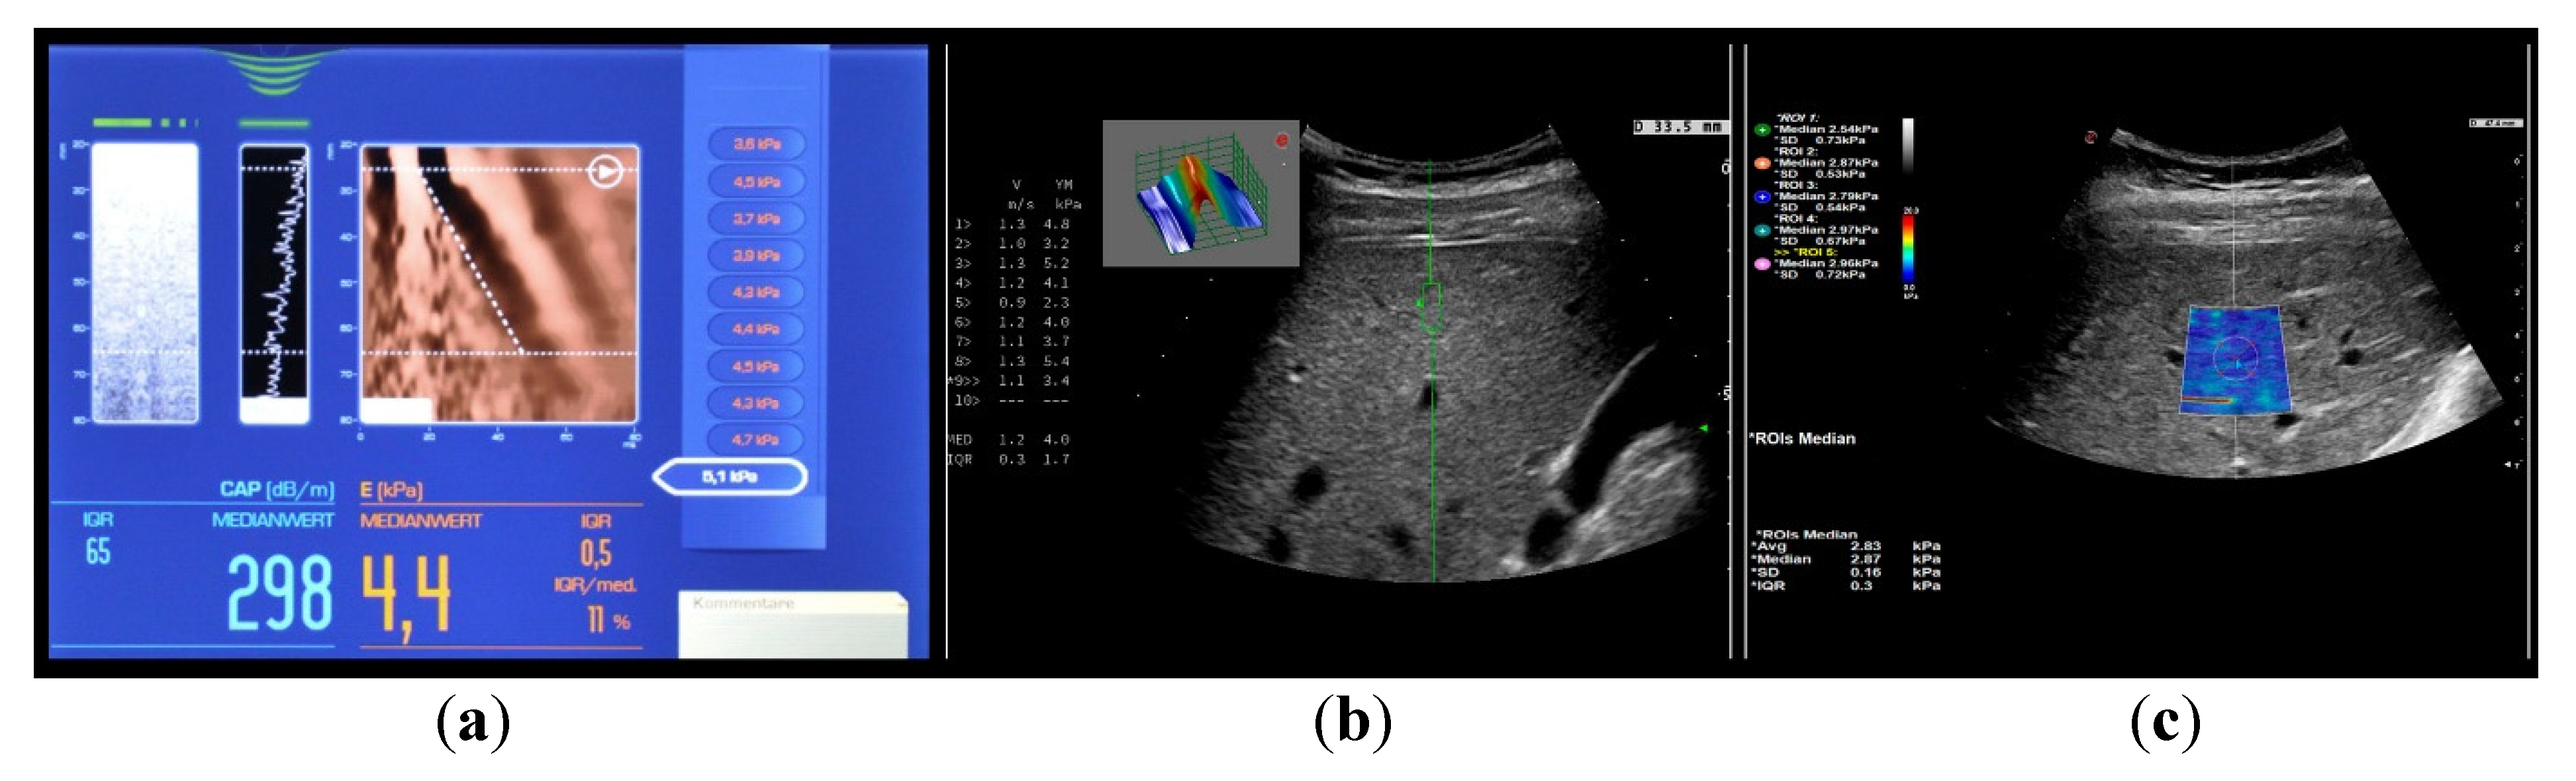

Figure 2 shows the most common used elastographic methods. Unless otherwise stated, the term elastography or elastographic examination in this article refers to the most common used method—transient elastography (TE; Fibroscan©).

TE is a unidimensional method in which a simultaneous ultrasound (US) representation of the investigated tissue is obtained as a simple M-mode picture (Figure 2). Other methods have integrated the elastography module into conventional abdominal US probes. This enables a morphological analysis of the organ in the grayscale with a superimposed measuring box in which the liver stiffness is measured. In point shear wave elastography (pSWE), the measuring box is small in size and there is no visible elastogram (Figure 2). If the measuring box is larger and has a visible elastogram (every point in the elastogram is color coded and represents different shear wave speeds), the method is called two-dimensional shear wave elastography (2D-SWE; Figure 2) [4]. The common advantage of all three modalities is that they are non-invasive, point of care and able to evaluate a greater volume of liver parenchyma with lesser variability and more quantitative specimen evaluation than liver biopsy which reduces sampling error in heterogeneously distributed liver disease processes [3].

Figure 2. US based elastographic techniques. (a) transient elastography; (b) point shear wave elastography; (c) 2D shear wave elastography.